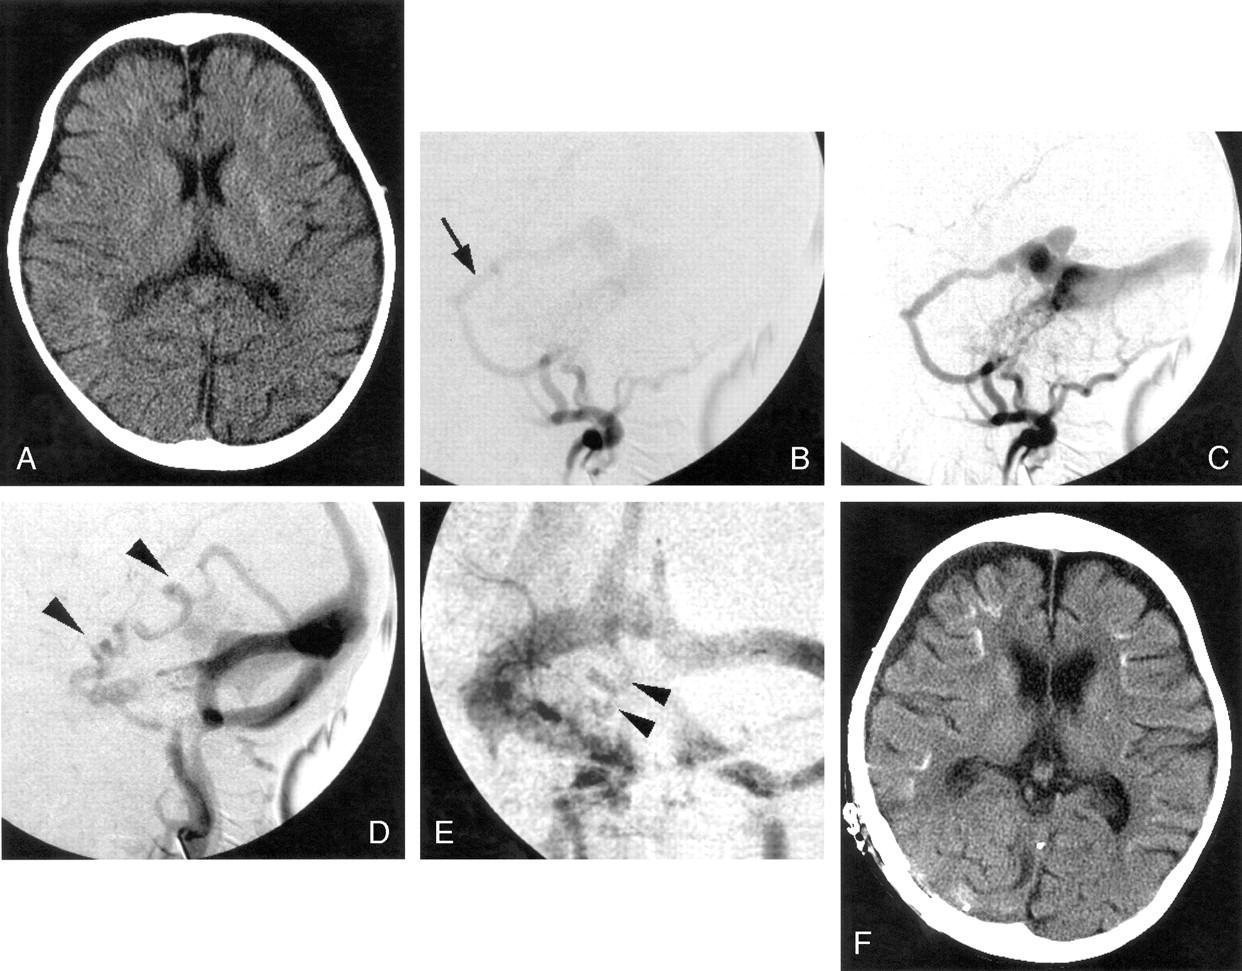

Case 1.

A, Precontrast CT scan shows curvilinear calcification (arrowhead) in the cortico-medullary junction at the inferior part of the left temporal lobe.

B, Postcontrast T1-weighted image shows multiple foci of curvilinear enhancement along the gyri, indicating dilated venous channels due to reflux (arrowheads).

C, Lateral view of left external carotid angiogram shows dAVF at left transverse sinus fed by the middle meningeal artery (arrow) and cortical venous reflux (arrowhead).

D, SPECT shows markedly reduced blood flow in the left temporal lobe where the cortical venous reflux was found.